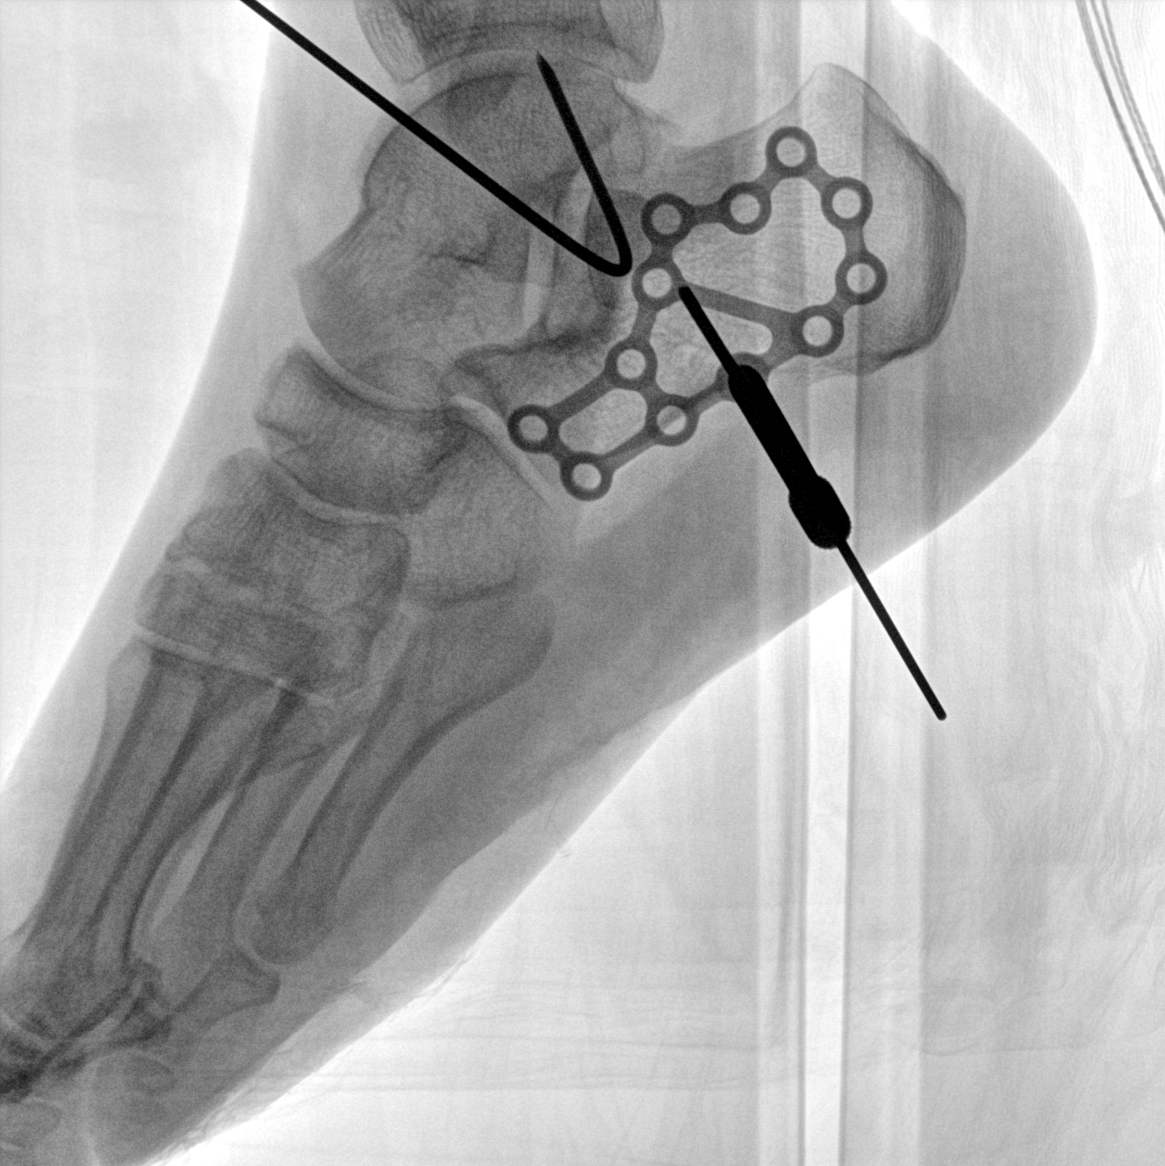

術(shù)中三維成像和橫斷面圖像提供多角度的手術(shù)診斷信息,輔助醫(yī)生進行術(shù)中評估判斷,諸如骨折復位情況和內(nèi)植入螺釘?shù)某叽绾臀恢茫o助手術(shù)更好地完成。